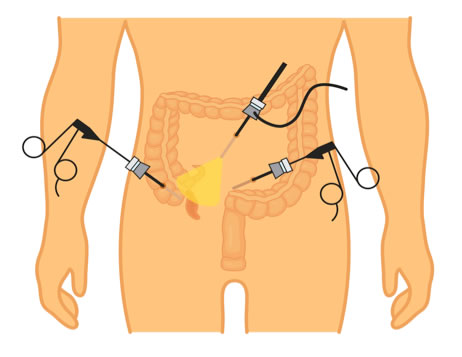

Σκωληκοειδεκτομή

Η σκωληκοειδεκτομή μπορεί να εκτελεστεί και λαπαροσκοπικά. Όταν η διάγνωση της οξείας σκωληκοειδίτιδας είναι βέβαιη, ο ρόλος της λαπαροσκοπικής προσπέλασης μάλλον περιορίζεται, αφού η «ανοικτή» σκωληκοειδεκτομή μπορεί να διενεργηθεί μέσω μιας σχετικά μικρής τομής και με μικρότερο κόστος. Ωστόσο η λαπαροσκόπηση έχει αξία αν η διάγνωση παραμένει αβέβαιη, ακόμα και μετά την περίοδο της παρακολούθησης, οπότε βοηθά και στη διάγνωση άλλων ενδοκοιλιακών παθήσεων σε περίπτωση απουσίας οξείας σκωληκοειδίτιδας, όπως πυελικής φλεγμονώδους νόσου σε γυναίκες αναπαραγωγικής ηλικίας.